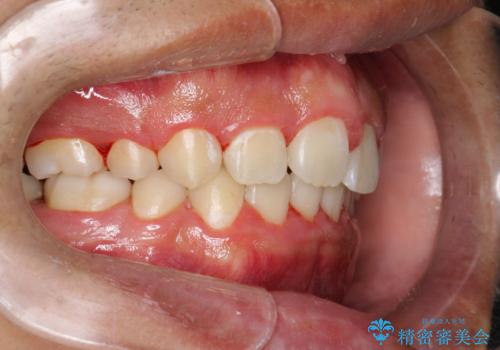

ワイヤー矯正終了時に装置除去と合わせてPMTC

- ワイヤー矯正の終了時にしばらく行っていないためクリーニングも希望されました。装置の除去j時にPMTC60分コースを行いました。

装置を除去すると、エナメル質にダメージがかかることなどがあります。除去の際、一緒にクリーニングを行うことで、エナメル質をなめらかにしたり、歯ぐきの引き締まりが見られます。また、歯ブラシだけでは取り除けない汚れも取り除きますので、歯の表面がツルツルになります。矯正治療中・終了時には合わせてPMTCを行うことがおすすめです。